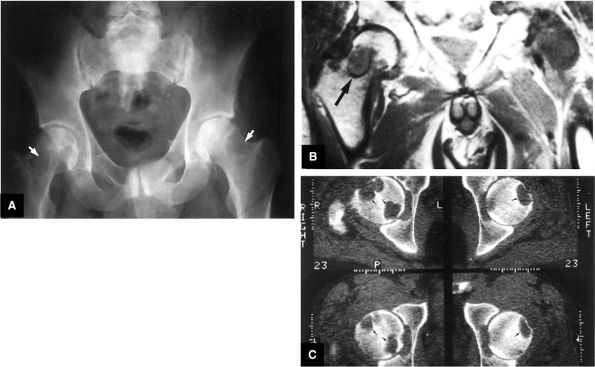

FIGURE 3.92 ● T1-weighted coronal images in LCP. (A) Normal femoral head capital epiphyses. (B) The earliest MR signs of LCP include peripheral irregularity of marrow-fat-containing epiphyseal ossification center (white arrows). Low-signal-intensity foci or linear segments are seen within the right and left ossification centers (black arrows). No subarticular collapse is present, and conventional radiographs are normal (TR, 500 msec; TE, 20 msec).

FIGURE 3.93 ● Coronal T1-weighted images show the spectrum of LCP from (A, B) early to (C, D) late advanced involvement. (A) Small, laterally displaced ossific nucleus with loss of yellow marrow signal intensity (long black arrow) is present early in the disease. Normal contralateral epiphyseal cartilage (curved arrow) and high-signal-intensity marrow (short black arrow) are seen. (B) Complete loss of right femoral epiphyseal marrow signal intensity (arrow) occurs as the disease progresses. (C) Bilateral low-signal-intensity osteonecrotic foci in the femoral epiphysis (arrows) become apparent later in the disease. Articular cartilage is thinner in the older child. (D) Advanced remodeling with coxa plana and coxa magna of the femoral heads (arrows) is indicative of late advanced involvement. (TR, 600 msec; TE, 20 msec.)